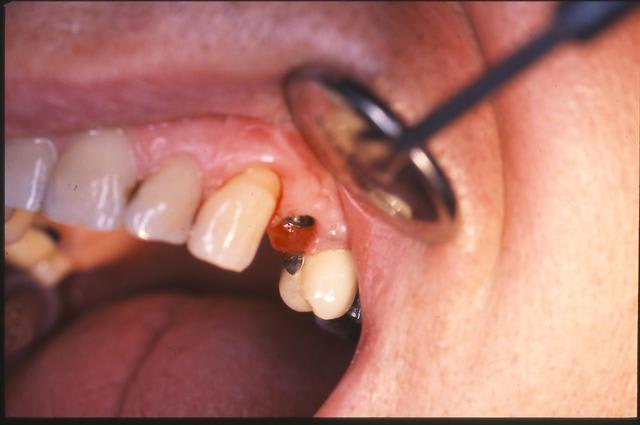

-fracture 25

-infection

-extraction (oups la ccm sur implant s'est descellée...)

-pas de pose d'implant car destruction de la paroi vestibulaire sur près de 5 mm

-pas de lambeau mais décollement vestibulaire muco-périosté à travers l'alvéole d'extraction et interposition d'une membrane de Collagen AT entre l'os et le périoste

-comblement BioOs et recouvrement avec même type de membrane

-conjonctif pédiculé tracté (comme j'ai pu) pour fermeture du site d'"extraction.